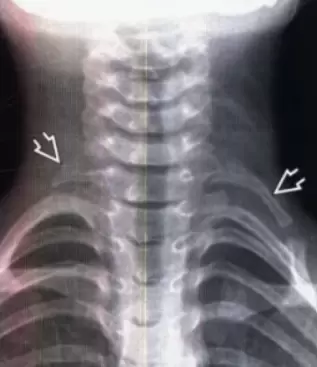

Согласно эпидемиологическим исследованиям, синдром встречается у около 5% населения. Наиболее часто наблюдается неврологическая форма, за ней следует венозная, в то время как артериальные варианты встречаются реже и могут проявляться в виде закупорки сосудов. Известно, что синдром добавочного шейного ребра также является распространенной причиной СГВ, хотя в большинстве случаев не вызывает каких-либо симптомов.

Анализ лечения 521 пациента, направленного на оценку эффективности хирургического вмешательства, показал, что наиболее частой причиной СГВ является компрессия плечевого сплетения, значительно чаще встречающаяся у женщин. Разные методы диагностики, такие как УЗДГ и рентгенография, играют ключевую роль в подтверждении диагноза и планировании хирургического вмешательства.